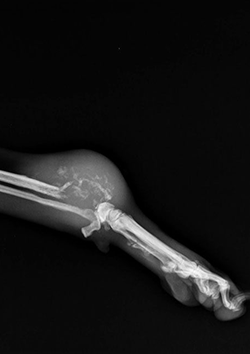

Unidad H: Tumores del sistema esquelético. Sarcomas de tejidos blandos